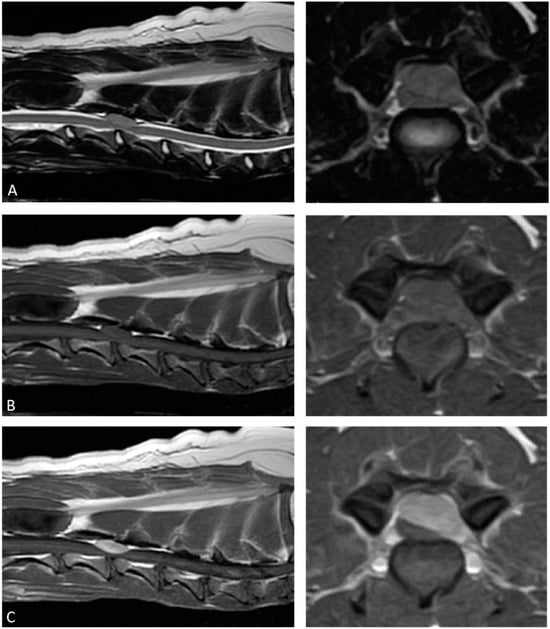

2. Case Description